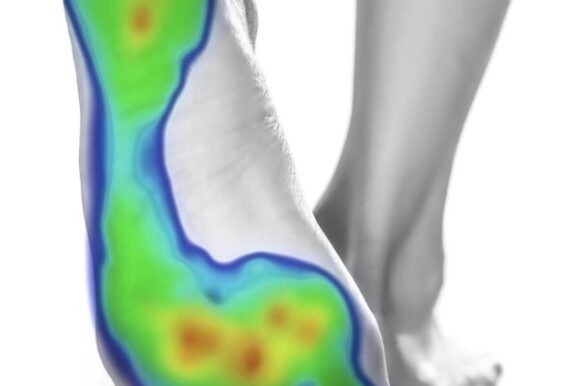

Beneficios del estudio de la pisada Prevención de lesiones y dolores crónicos. Alivio…

Un tratamiento a medida Las ortesis plantares no solo son un tratamiento correctivo…